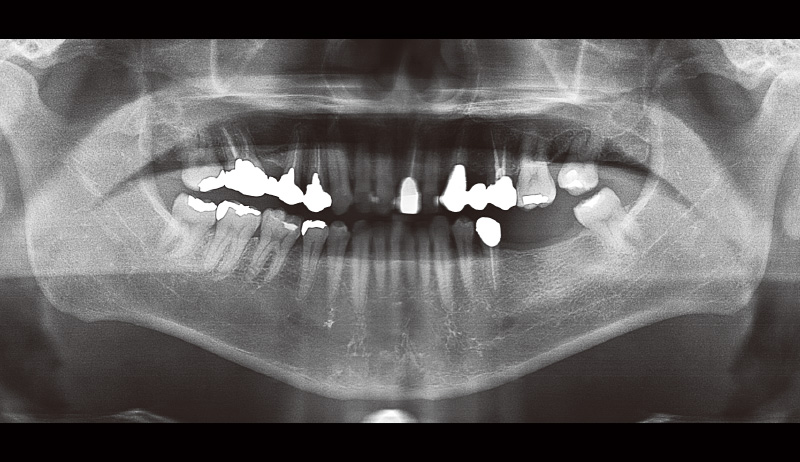

51歳男性、主訴:左下の奥歯で噛めるようになりたい(図14, 15)。

この症例が私にとって初めてのSPIインプラント症例だった。ドリルキットがとても簡便で操作性も良く感じた。こちらの症例は初心者でもできる症例を挙げているので参考にしていただけたらと思う(図16~19)。

まずフラップを開く前にヨード染色を行い、付着歯肉の幅を確認する。その後、フラップを全層弁で開く(私の場合はそこまで大きくは開けないことが多い)。床形成を行い平行指示ピンを入れ平行性を確認。SPIイニセルインプラントをコンディショニングした状態で埋入の準備を行う。₅:φ4.0長さ11mm、 ₆:φ4.5長さ11mmのSPIイニセルインプラント エレメントRCを埋入。付着歯肉を減らさないように縫合を行った。

![[写真] 初診時のパノラマX線写真](/academic/dentalmagazine/wp-content/uploads/sites/2/2025/09/194-8_photo15.jpg)

図15 初診時のパノラマX線写真 -

![[写真] インプラント埋入後のパノラマX線写真](/academic/dentalmagazine/wp-content/uploads/sites/2/2025/09/194-8_photo17.jpg)

図17 インプラント埋入後のパノラマX線写真(₅のヒーリングキャップが甘く締められていることを確認したので再度締め直しを行った)。 -

![[写真] 完成後のパノラマX線写真](/academic/dentalmagazine/wp-content/uploads/sites/2/2025/09/194-8_photo18.jpg)

図18 完成後のパノラマX線写真 -